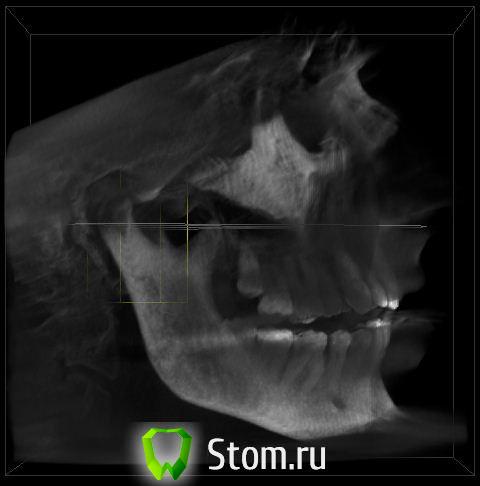

Aldo Rain Опубликовано 22 ноября, 2011 Поделиться Опубликовано 22 ноября, 2011 Для тогоХм.. Хотелось бы разобраться, к чему готовиться через 2-5-10 лет? Какие варианты решения проблемы возможны? Есть ли какие-то превентивные методы? Эстетика волнует, но не так что бы уж очень сильно.Для того, чтобы разобраться в причинах стираемости необходима дополнительная информация, как минимум боковая Телерентгенограммаhttp://i016.radikal.ru/1102/d4/3815a0b09a4b.jpg И анализ моделей в артикуляторе http://s014.radikal.ru/i326/1109/6d/e7320190a586.jpg Ссылка на комментарий

Oleg-Gru Опубликовано 22 ноября, 2011 Автор Поделиться Опубликовано 22 ноября, 2011 Да уж... Почему-то вспомнилась поговорка о благих намерениях устилающих дорогу в ад. На самом деле есть более чем один повод разобраться с ВНЧС. Несколько лет страдаю от ушного шума. Говорят, что это тоже может быть связано с суставом. К сожалению боковой телерентгенограммы пока нет. Есть только КТ. Можно что-то сказать по этим снимкам? Если нет, то сделаю рентген и повешу тут через пару дней. Ссылка на комментарий

Снежана Опубликовано 22 ноября, 2011 Поделиться Опубликовано 22 ноября, 2011 КТ вполне возможно подойдет ортодонту. я бы сходила сделать анализ, выслушать что есть чего нет, что можно предпринять, вот тогда и принимать решение) Ссылка на комментарий